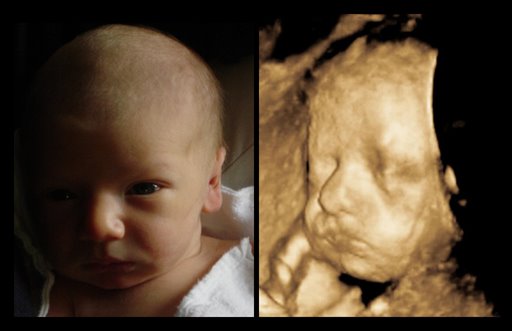

Difference Between 3d Ultrasound Scans And 4d Ultrasound Scans By

3d Scanner Image 3d Sonogram

See My Baby Ultrasound Inc Pregnancy Ultrasound